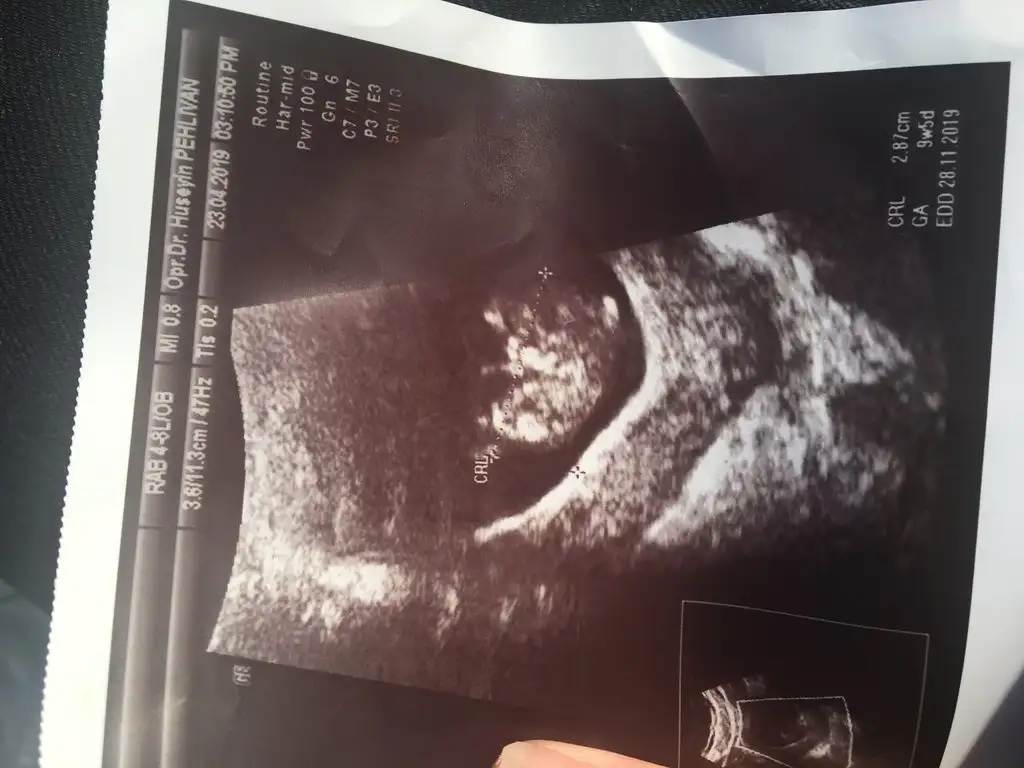

Kızlllar büzde 9+5 olmuşuz 🧿💕 ilk defa kalbıni duyduk kalp atımı 165 çok iyi dedi sadece suyu bol iç dedi su az dedi :( doğru söyledi su içmem durdu resmen midem bulanıyor resmen sizler nasıl yapıyorsunuz su içmek için lımonlu içsem acaba zararlı olurmu bilemedim bide resmini atsam tahmin yürütürmüsünüz kızlar cok merak ediyorumm 😍😍😬😬🙏🏼🙏🏼🙏🏼